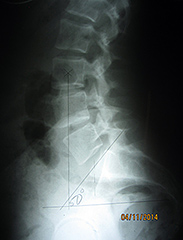

Lateral Lumbar

The lateral lumbar provides a wealth of information. Ferguson's gravity line is important, as it represents the athlete's center of gravity from the side. This marking originates in the center of L3, with a plumb line drawn straight downward. This line should bisect the anterior third of the sacral base. In Figure 7, we can see the line falls anterior to the norm. This finding produces increased stresses on the posterior structures of the spine, such as the pars and facets. Dr. Yochum has concluded that no one has ever been born with a pars defect, as pars defects are stress fractures that typically occur during adolescence. The incidence of pars defects increases with extension activities of the low back, as well as with an increased sacral base angle and an anterior Ferguson's gravity line.

Fig. 7: Anterior Ferguson's Line

In Figure 8, we see Ferguson's gravity line is posterior, suggesting the body's weight bearing is increased over the posterior disc and spinal nerve root. This increased stress, over time, will predictably increase disc injuries and nerve root irritations.

Fig. 8: Posterior Ferguson's Line